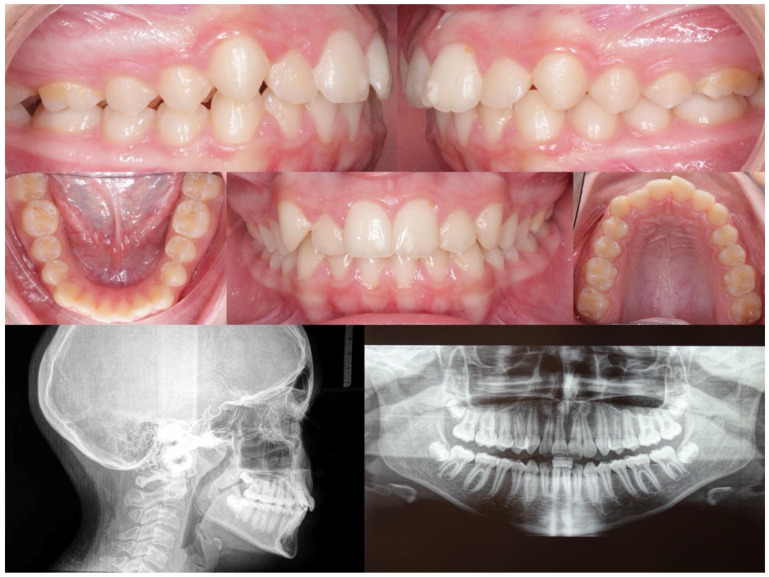

Background and Objectives: This study aimed to evaluate the outcomes of Class II subdivision teenage patients treated with Invisalign® clear aligners (CAs) and elastics. Materials and Methods: A total of 23 individuals aged 14.3 ± 2.5 years were enrolled in this study. The participants were divided into Group 1 (mandibular midline deviation) and Group 2 (maxillary midline deviation). The midline deviation from the facial midline; anteroposterior discrepancy; overjet (OJ), overbite (OB), and Peer Assessment Rating (PAR) scores; upper incisor and lower incisor (L1) positions; and angulation were measured at the beginning (T0) and end (T1) of the orthodontic treatment. Results: Group 1 showed significant higher variations in OJ (-2.3 ± 2.3 vs. -0.6 ± 0.8, p < 0.001), OB (-2.1 ± 2.3 vs. -1.1 ± 1.4, p < 0.001), PAR score (-32.0 ± 11.7 vs. -27.3 ± 13.1, p < 0.001), L1-to-mandibular-plane angle (-3.6 ± 7.0 vs. -1.3 ± 3.2, p < 0.001), and interincisal angle (10.07 ± 8.7 vs. 5.9 ± 5.3, p = 0.007). The midline deviation was the only measurement with higher variation in Group 2. The average distance between the mesiobuccal cusp of the maxillary first molar and the buccal groove of the mandibular first molar was 0.3 ± 0.5 mm. Conclusions: A total of 21 patients achieved bilateral Class I (91% success rate) and demonstrated great improvement (72-96%) in PAR scores. Regardless of the etiology of malocclusion, the orthodontic correction of the Class II subdivision with CAs showed high accuracy and predictable results.

Abstract Image